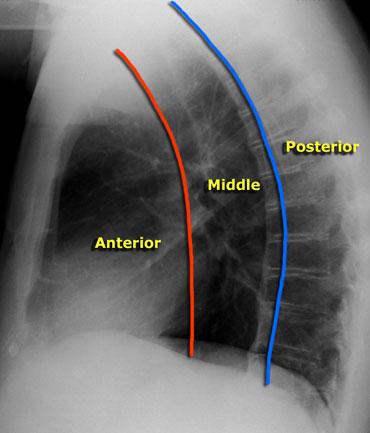

Trung thất có thể được chia thành các khoang trước, giữa và sau.

Cần lưu ý rằng không có mặt phẳng mô nào phân tách các khoang này.

Trên phim chụp X-quang tư thế nghiêng, khoang trước và khoang giữa có thể được phân tách bằng cách vẽ một đường tưởng tượng ở phía trước khí quản và phía sau tĩnh mạch chủ dưới.

Khoang giữa và khoang sau có thể được phân tách bằng một đường tưởng tượng đi qua điểm cách bờ trước thân đốt sống 1 cm về phía sau.

Cách phân chia này giúp chúng ta thu hẹp chẩn đoán phân biệt một cách hiệu quả hơn.

Tại nhiều cơ sở y tế, chụp CT được thực hiện để phân tích và đặc trưng hóa thêm các khối trung thất trước và giữa.

MRI thường được chỉ định để đánh giá các khối nằm ở khoang sau, do phần lớn các khối này có bản chất nguồn gốc thần kinh.

CT bổ sung có thể được thực hiện khi cần đánh giá cấu trúc xương.